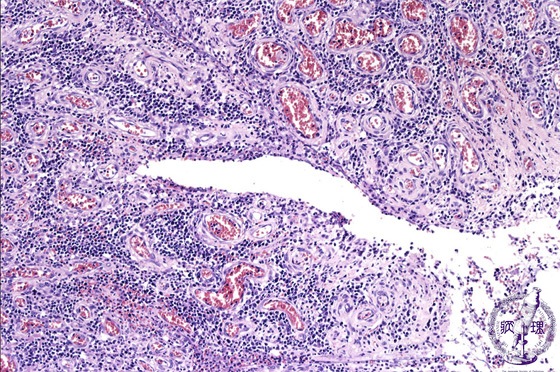

Microscopic view (H&E stain, medium power): Fissure formation is seen.